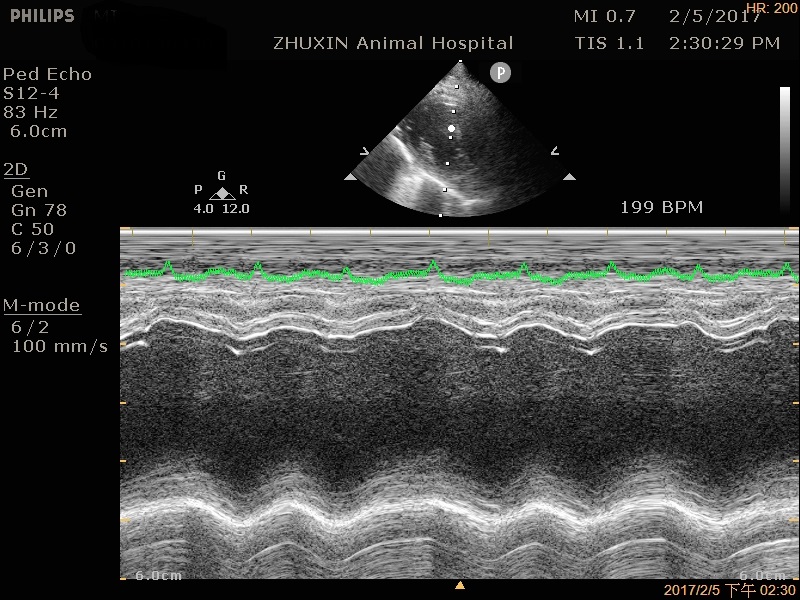

擴張性心肌病的超音波影像

肺積水導致呼吸困難的四歲貓-咪咪,在築心緊急給氧氣治療及利尿後終於脫離危險,而進一步進行超音波掃描,診斷為擴張性心肌病,詳細詢問主人生活情況後發現有長期吃狗飼料的問題,提醒毛爸毛媽,貓咪相對狗狗需要較多的脂質和蛋白質,狗狗飼料無法給予貓咪足夠的營養,長期下來可能會造成眼睛失明、耳聾或心臟病等疾病問題。然而這種情況下所引起的心臟病,是有機會痊癒的!所以建議有任何心臟疾病問題的毛小孩,一定要由專業的醫師及專門的心臟超音波設備來檢查、確診,才可以更加了解毛小孩的身體狀況而對症下藥喔!

肺積水導致呼吸困難的四歲貓咪--咪,緊急給氧及利尿後脫離危險,經超音波掃描診斷為擴張性心肌病,詳細詢問生活情況後發現為長期吃狗飼料所引起的心臟問題,這樣的心臟病是有機會痊癒的喔!!!!!